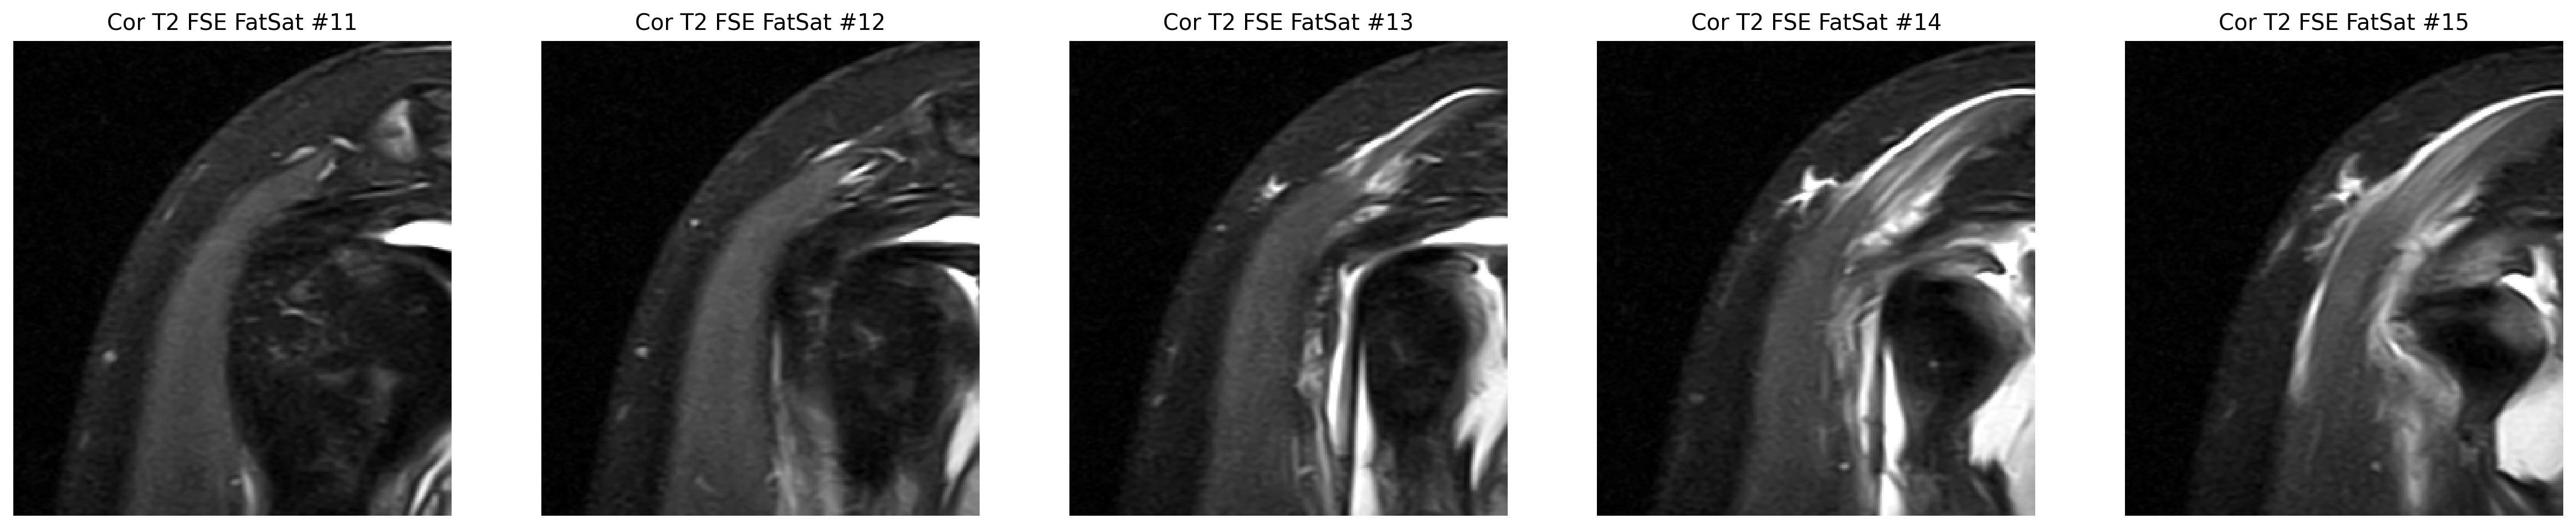

The strongest image-only read is a smaller tear or split on the joint-facing side of the supraspinatus tendon where it attaches to bone.

The cuff finding was checked in coronal and sagittal views, while the labrum was reviewed on axial arthrogram slices.

The space that cushions the tendon looks irritated and fluid-filled, which commonly travels with cuff problems.